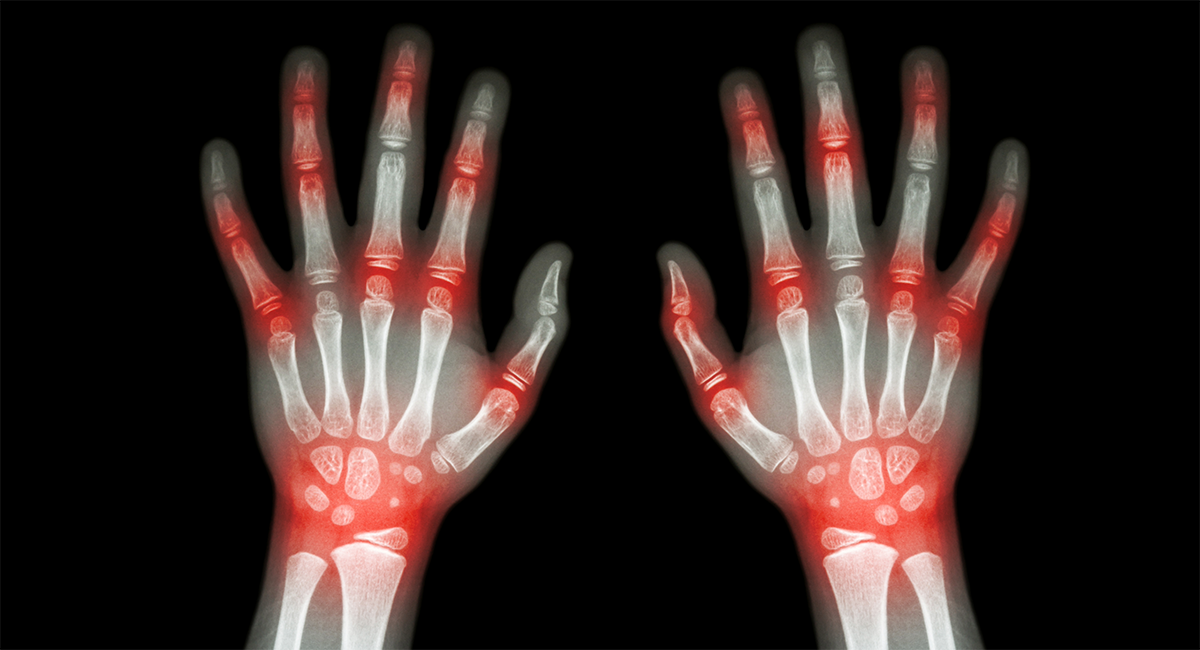

— рентгеновское исследование и компьютерная томография (КТ). Они необходимы для определения характера и распространенности патологического процесса, а также его стадии. КТ позволяет получить послойное изображение тканей и оценить внутренние структурные изменения;

— артроз суставов. Проявляется дегенеративными изменениями хрящевой ткани суставных поверхностей, сужением суставной щели. В результате кости, формирующие сустав, сближаются, соприкасаются и травмируют друг друга при движении. Компенсаторно возникают избыточные разрастания костей — остеофиты, форма сустава нарушается, и деформация становится внешне заметной;

— артрит — инфекционный (при попадании инфекции в полость сустава) или аутоиммунный, например, ревматоидный. В суставе развивается воспалительный процесс, сопровождающийся деструкцией и отеком. Сустав внешне увеличивается в размерах, кожа над ним краснеет и становится горячей. Хроническое течение воспаления приводит не к столь бурным, но непрерывно продолжающимся разрушениям, которые не могут не сказаться на форме сустава;

— подагрический артрит — приступообразно обостряющееся воспаление суставов, связанное с метаболическими нарушениями. В период обострения суставы отекают, увеличиваются, становятся горячими на ощупь. При длительном течении заболевания на суставах образуются своеобразные шишки — тофусы из-за локального скопления солей мочевой кислоты;